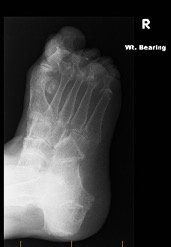

Rheumatoid arthritis is an auto-immune systemic condition that can involve multiple joints in the body. A high percentage of people with rheumatoid arthritis develop symptoms related to their foot or ankle. Symptoms normally commence in the small bones and joints of the toes and forefoot. They can then progress to the joints in the back of the foot known as the rearfoot and ankle. There are other forms of inflammatory arthritis that affect the foot and ankle including gout, ankylosing spondylitis and psoriatic arthritis. Patients with these conditions are almost always under the care of a Rheumatologist who is a specialist of joint disease.

The exact cause of rheumatoid arthritis is unknown however there are several theories including a genetic predisposition and a chemical or environmental trigger to activate the disease. As an auto-immune condition, the body’s defence system turns on itself and produces substances that attack and inflame its own joints. With 25% of the body’s total bones being located in the foot and ankle, it makes sense this condition is commonly encountered in the foot and ankle.